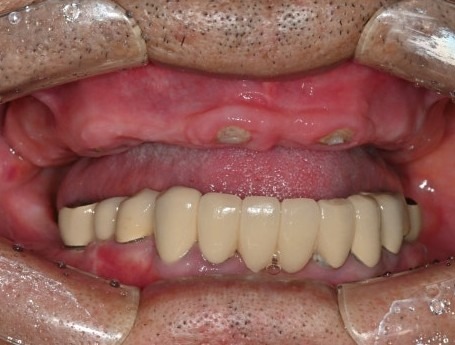

수술 당일

수술 2일 후

수면마취로 17개의 임플란트를 식립하였고,

월요일에 임플란트 즉시 기능 치아(임시치아)를 끼워드렸습니다.

치료 전

수술 2일후

몇 개월이고 기약 없이 임시 틀니를 써야한다는 걱정에

치료를 시작하지 못하셨던 환자분은

수술 2일 만에 고정된 치아가 완성되자

놀라워하시면서 식사가 가능하게 된 걸

너무 좋아하셨습니다.